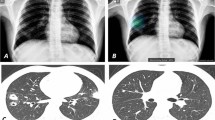

Diagnostic images of 74-year-old female patient with adenocarcinoma in the left upper lung. a Chest radiograph showing a nodule in the left upper lung masked by the left clavicle and first rib (arrowhead), with a visibility score of 3 and a background lung score of 2. b The nodule was properly detected by CAD with a probability of 60. c Chest computed tomography showing a part-solid nodule with a solid part of 2.2 cm in size

Diagnostic images of a 74-year-old male patient with squamous cell carcinoma in the right lower lung. a Chest radiograph showing a nodule in the right lower lung masked by the diaphragm (arrowhead), with a visibility score of 2 and a background lung score of 4. b The nodule was properly detected by the CAD with a probability of 83, with two non-target areas were detected with probabilities of 47 and 32, respectively. c Chest computed tomography (CT) showing a solid mass measuring 4.6 cm in size. d CT did not reveal any abnormality on the lesion with a score of 32, which was considered a non-target normal area. e CT revealed fibrosis on the lesion with a score of 47, which was considered a non-target abnormal area